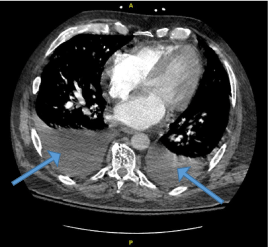

A 62-year-old Caucasian male with a medical history of essential hypertension, deep venous thrombosis, on oral anticoagulant, and obesity presented to our facility due to sudden onset moderate substernal chest pain exacerbated upon exertion and associated with severe dyspnea, requiring supplemental oxygen. His blood pressure was 126/56 mmHg and his pulse rate were 92 beats per minute. The patient was noted to have a 3/6 pansystolic murmur loudest in the aortic region and radiating to the neck. Crackles were noted in the left lower lung lobe. Initial troponin was 0.679 ng/mL and N-terminal prohormone of brain natriuretic peptide (NT-proBNP) 14,058 pg/mL. Other pertinent laboratory findings are noted in [Table 1]. Electrocardiogram (ECG) revealed sinus rhythm with premature supraventricular complexes, nonspecific ST changes. He was administered full-strength aspirin, heparin drip was initiated, and he was admitted to the cardiovascular service. Chest radiograph revealed findings consistent with pulmonary edema, otherwise was largely unremarkable. Venous doppler lower extremity ultrasound was negative for deep venous thrombosis (DVT) and computed tomography angiography (CTA) of the chest was negative for pulmonary embolism (PE) but revealed findings suggestive of mild congestive heart failure with moderate bilateral pleural effusions [Figure 1].

Figure  1.  CT chest demonstrating moderate  bilateral pleural effusion suggestive of mild CHF (blue arrows)